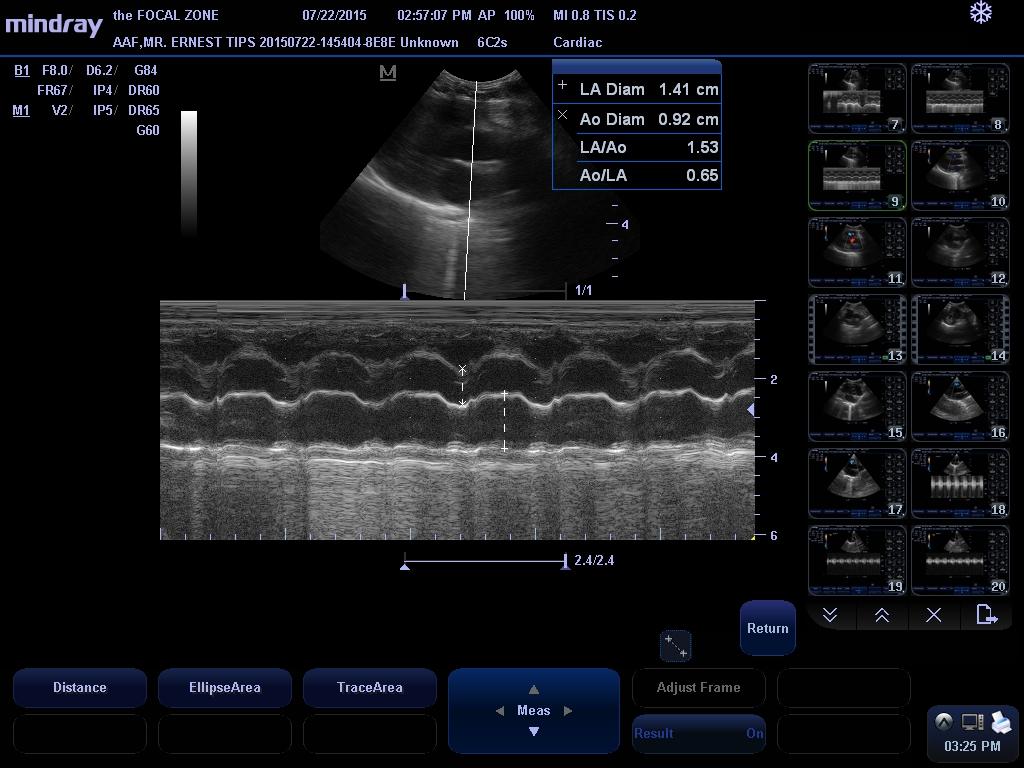

LA/Ao – 1.53

IVSd – 4.6 mm

LVIDd – 16.7 mm

LVPWd – 3.8 mm

LVIDs – 8.2 mm

FS – 50.8%

EF – 84.9%